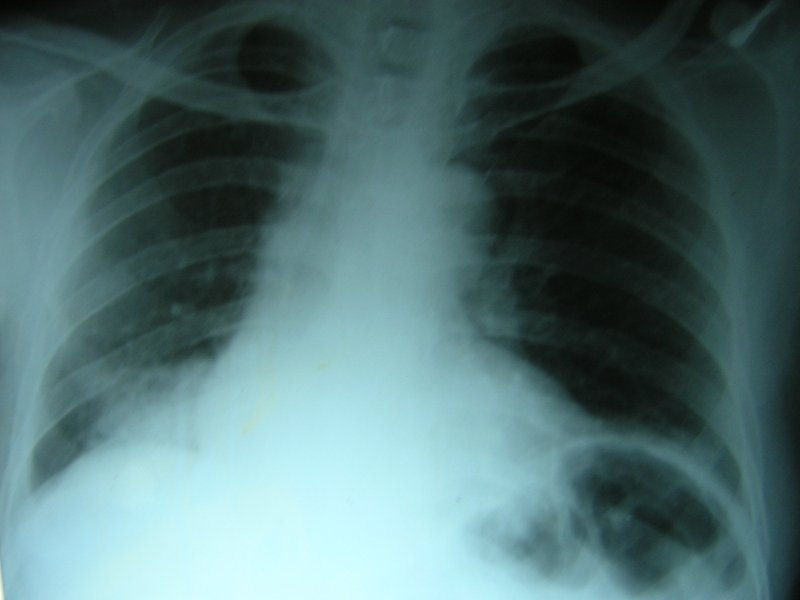

A 65-year-old man was referred to our chest clinic for preoperative assessment before undergoing repair of a fractured neck of his femur. His chest radiograph was abnormal (figure 1).

Figure 1: Chest radiograph showing right lower lobe consolidation.

The chest radiograph and CT scan show an opacity with air bronchogram indicating a consolidation or pneumonia picture. Only silicosis of the listed causes does not generally cause lower lobe consolidation. The chest radiograph showed no evidence of resolution after an adequate course of antibiotics characterizing this as a non-resolving pneumonia.